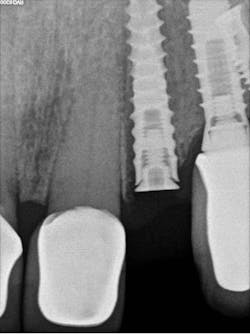

Case report: Extraction/immediate implant placement with provisional, using the Ditron Ultimate Implant System

- Radiographic findings: Fractured lateral incisor with periapical pathology

- Implant: Ditron Ultimate 3.75 x 16 mm

- Abutment: Final straight 11.5 mm titanium abutment delivered at time of implant placement